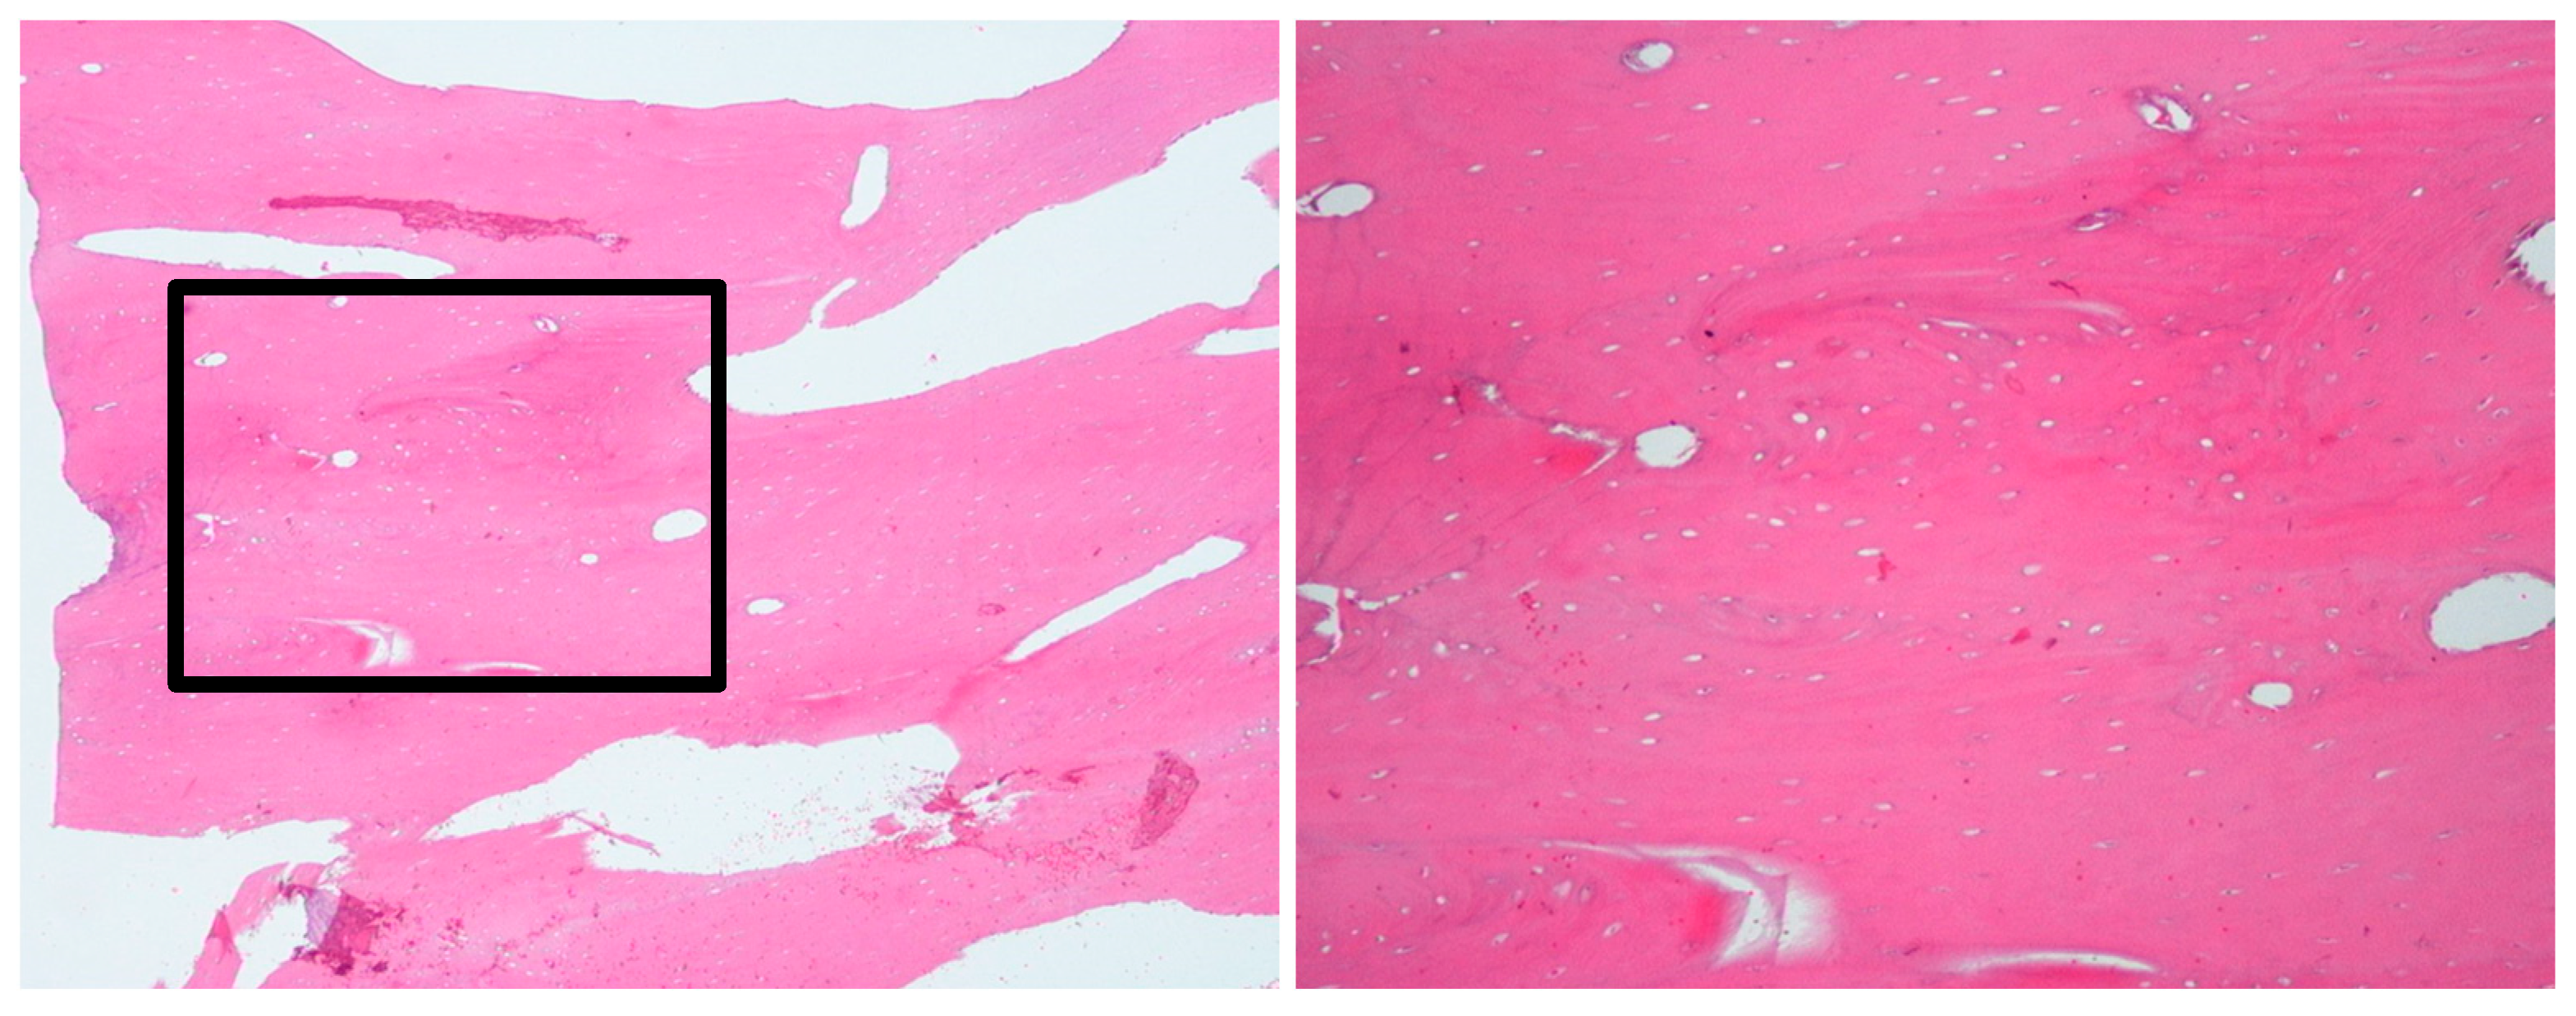

2.1.3. Histopathological Examination

2.2.3. Histopathological Examination

2.3.3. Histopathological Examination

2.4.3. Histopathological Examination

| 1 | 11 | Left mandible (#32–#37) | Mixed sclerotic and lytic lesion with buccolingual expansion and “onion-skin” periosteal reaction | Irregular bone and fibrous tissue, sclerosis, no inflammation or bacteria | Long-term antibiotic course, NSAIDs | CNO confirmed by imaging, histology, and initial failure to respond to antibiotics | Conservative; antibiotics discontinued after improvement | Improved at 7 months; recurrence at 18 months; no further treatment needed |

| 2 | 9 | Right mandible (#33–#47, crossing midline) | Patchy sclerotic and radiolucent lesion, mandibular expansion, double cortex | Viable bone with osteoblastic rimming, no bacterial colonies | Multiple antibiotics, extractions, NSAIDs | CNO based on imaging, histology, and clinical course | NSAIDs only; progressive improvement | Gradual resolution with NSAIDs |

| 3 | 10 | Right mandible (#34–#47, crossing midline) | Granular sclerotic and radiolucent lesion, moth-eaten pattern, layered periosteal reaction | Normal viable bone, sterile | Empirical antibiotics, paracetamol, NSAIDs | CNO confirmed by imaging, CT, and sterile biopsy | NSAIDs only; no need for further escalation | Progressive improvement; under observation |

| 4 | 12 | Left mandible (#37–#43, crossing midline) | Irregular mixed sclerotic/lytic lesion, periosteal reaction, buccolingual expansion | Viable bone with no bacterial colonies | Empirical antibiotics, paracetamol, NSAIDs | CNO confirmed based on recurrence, imaging, and histology | NSAIDs only; no additional therapy needed | Gradual clinical improvement; no recurrence noted |